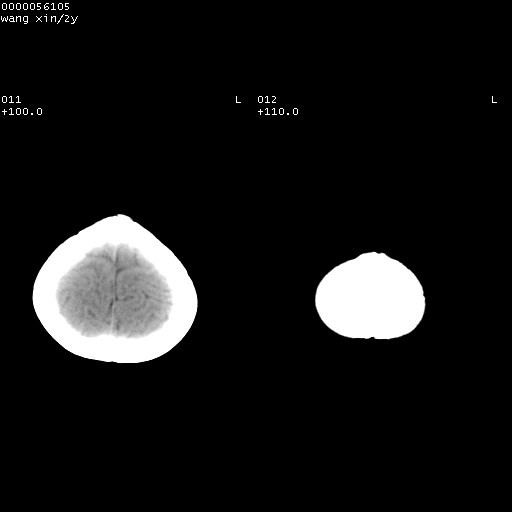

标题: PED1611:F,2Y。右侧额部小包块,光整,质硬,边界清楚,无 [打印本页]

标题: PED1611:F,2Y。右侧额部小包块,光整,质硬,边界清楚,无

右额骨内板压迫性变薄,呈椭圆形膨胀性骨吸收和低密度区,其间可见小斑片状致密影,-支持表皮样囊肿